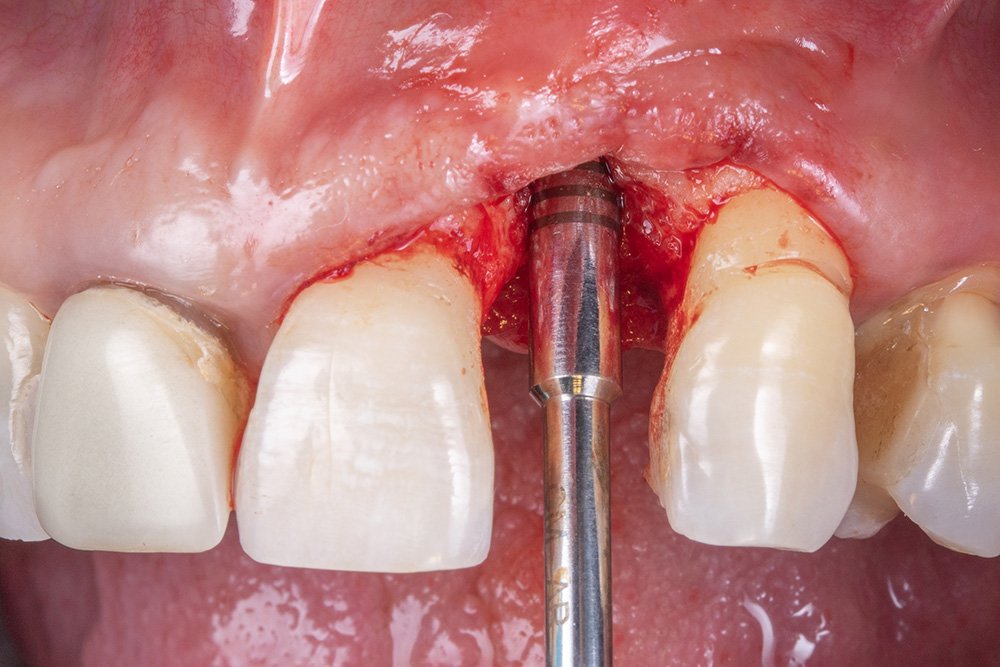

Ao final da instalação do implante, é importante mensurar a distância do implante intraósseo, devendo ficar de 2 a 3 mm, considerando a mucosa peri-implantar.

Para a escolha do munhão, componente responsável por receber a peça protética, foi utilizado o pilar reto da linha IDEALE (Implacil De Bortoli).